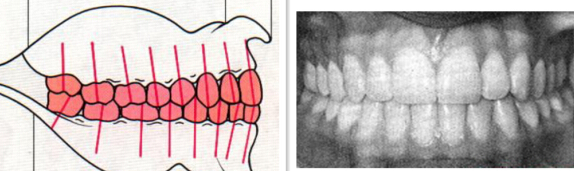

拔牙後內(nei) 收牙齒

如果輕微的齙牙是牙齒排列造成的,而且有嚴(yan) 重牙齒擁擠的情況,可能需要拔牙,這樣才能內(nei) 收牙齒,讓牙齒回歸到正常的牙齒排列中,而且矯治後美觀結果也會(hui) 更好。當然,如果是頜骨問題造成的輕微齙牙,可能拔牙也解決(jue) 不了問題。